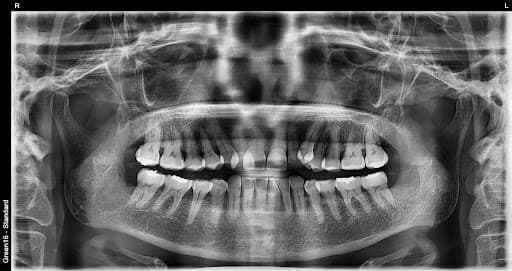

横生智齿

横向生长会挤压 相邻的牙齿

复杂的阻生智齿 - 即使深埋在牙龈中也没问题

贴近神经的智齿 - 无需担心神经损伤,安全拔除

水平阻生智齿 - 即使是横向生长的困难案例也可以处理